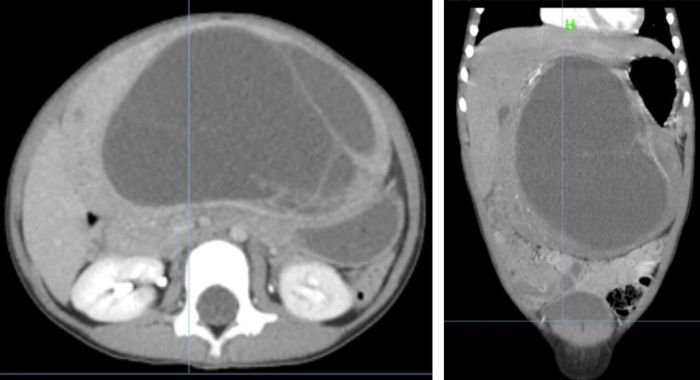

据悉,这位4岁的患儿因腹腔长了一个“足球”大小的肿瘤而备受病痛折磨,这个肿瘤不仅让孩子腹部胀痛难忍,还影响了正常的消化功能和生长发育。患儿家属经多方打听,来到了贵州医科大学第二附属医院。普外科团队在了解患儿病情后,迅速为该患儿安排了全面细致的检查。术前影像结果提示患儿中上腹腔有一巨大囊实性肿瘤,具有恶性倾向,并且已对患儿腹腔脏器形成挤压,亟须手术治疗。

术前CT图像

术中探查发现,该肿瘤直径约20cm,占据了该患儿腹腔的中上部,致其腹腔内器官严重受压,影响正常功能。并且该肿瘤与肝脏尾状叶粘连致密,其滋养血管来源于下腔静脉,整个肿瘤基底部与下腔静脉生长密切。普外科团队凭借精湛的医术和丰富的经验,犹如刀尖上的舞者,小心翼翼地剥离肿瘤,避免了术中副损伤及大出血。经过数小时的紧张奋战,终于完整地切除了肿瘤,手术取得了圆满成功。